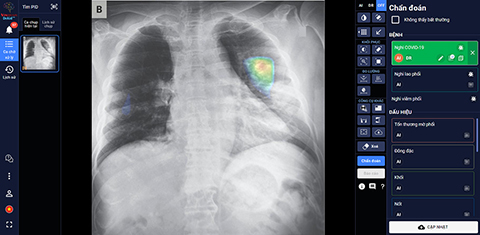

Launched on June 14th, 2020 as an intelligent assistant for radiologists, “DrAid for Radiology” is the first product of VinBrain and also the first complete AI product of healthcare in Viet Nam. The product is capable of detecting and screening over 21 abnormal signs and pathologies of Lung - Heart - Bone within 5 seconds with an accuracy of over 89 per cent and sharing diagnostic results via QR code or link. In particular, it is capable of self-warning of COVID-19, including asymptomatic cases or mild lung injury based on upright chest X-Ray and improving accuracy in addition to reducing false negatives when being used in combination with PCR test. DrAid also features the (remotely) “Consulting a second doctor” function. Enabled by images shared directly from DrAid, doctors can remotely consult with colleagues or leading experts without being affected by geographical barriers.

DrAid was highly appreciated by the ACM SIGAI selection committee because of its combination and application of the most state-of-the-art AI techniques, such as multi-class classification and structured prediction, active learning, adversarial training, convolutional networks, speech recognition for automatic medical report editing, lesion localization on medical images with machine learning using high-tech AI based on models with hundreds of millions of pixel parameters and big data of millions of images of millions of pixels each, among others, into a comprehensive health care AI service.